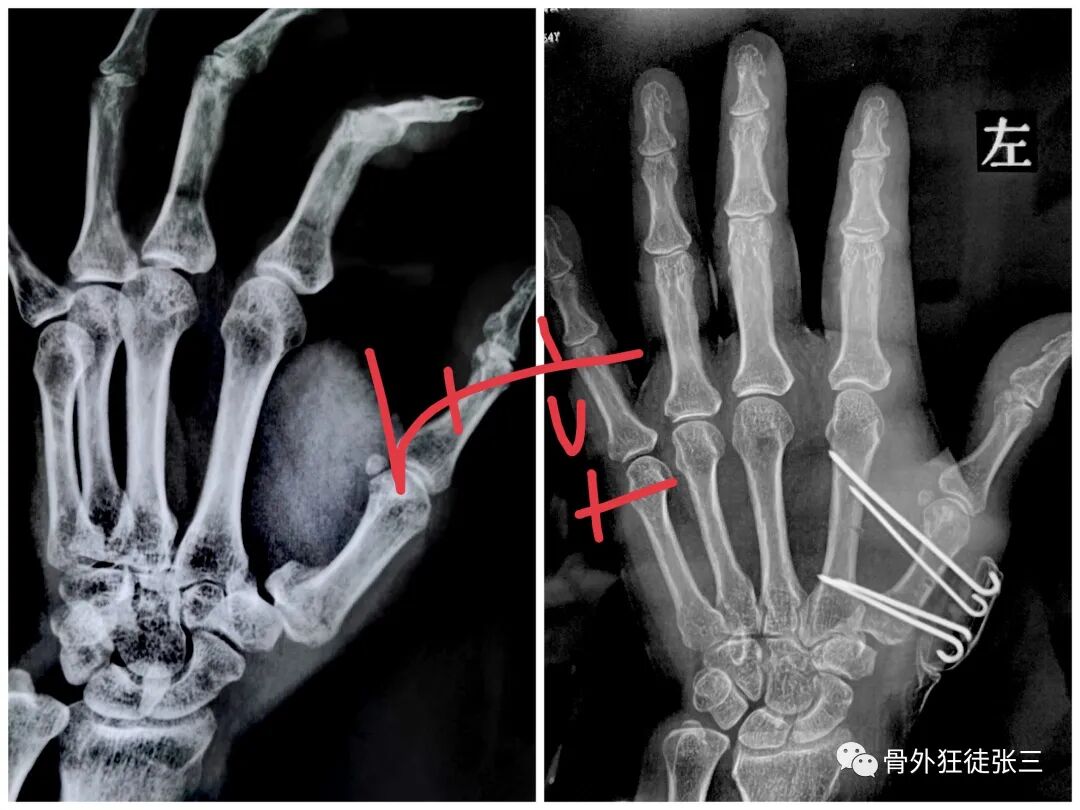

病例20,陈旧性第5掌骨头骨折,畸形,闭合复位,克氏针支架

病例22,陈旧性第5掌骨骨折,畸形,闭合复位克氏针支架